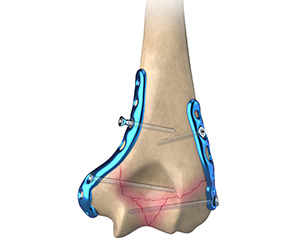

ORIF of the Distal Humerus Fractures

A distal humerus fracture is a condition that occurs when there is a break in the lower end of the humerus bone that commonly occurs as a result of severe trauma.

ORIF of the Humerus Fractures

Open reduction and internal fixation (ORIF) of humerus fractures is a surgical technique employed for the treatment of humerus fractures to restore normal anatomy and improve range of motion and function.